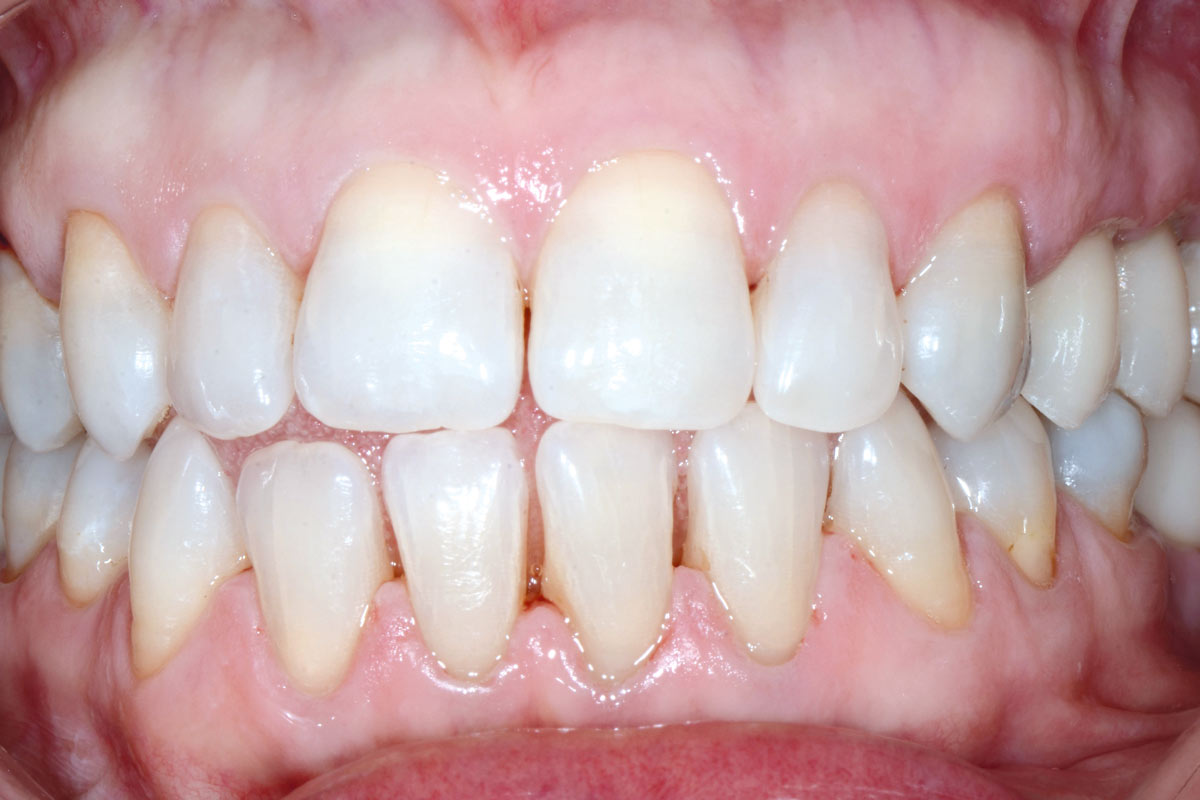

2/13 - Clinical situation before teeth extraction

Multiple socket preservation in the maxilla with collacone® max – Dr. D. Jelušić